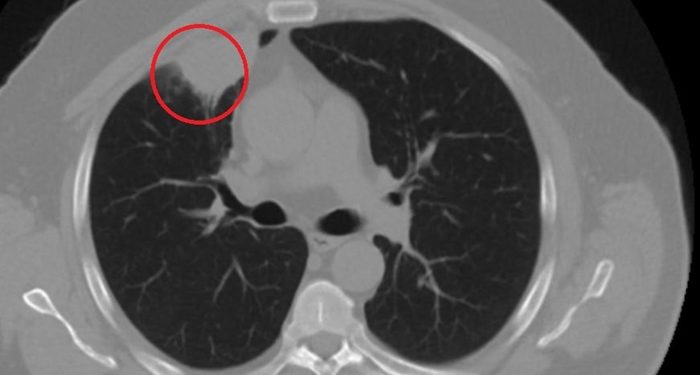

Cumhuriyet’in haberine göre, şehir dışında çalışan N.T.’nin, göğüs ağrısı şikayetiyle gittiği hastanede çekilen tomografisinde sağ akciğerinde 4 santimetre çapında tümör tespit edildi. Kanser olabileceği şüphesiyle yapılan ileri tetkikler sonrası N. T.’ye akciğer kanseri teşhisi kondu ve acil ameliyat kararı verildi. Bunun üzerine N.T., ameliyat için memleketi Kahramanmaraş’a geldi. Sütçü İmam Üniversitesi Sağlık Uygulama ve Araştırma Hastanesi Göğüs Cerrahi Anabilim Dalı Öğretim Üyesi Dr. Fatoş Kozanlı da tomografi ve test sonuçlarına göre N. T.’ye akciğer kanseri teşhisi koydu ve ameliyat yapılması gerektiğini söyledi.

“Hastamız, çalıştığı başka bir kentte göğsünden darbe alıyor ve ağrıları geçmeyince bir üniversite hastanesine başvuruyor. Burada hastaya bir akciğer grafisi çekiliyor. Sağ akciğerinde bir kitleye rastlanıyor. Daha sonra hastaya, bir akciğer tomografisi çekiliyor ve göğüs cerrahisi için önemli büyüklükte olan 4 santimetre çapında, akciğer kanserine benzer özellikte radyolojik bulgular olan bir kitle tespit ediliyor. Daha sonra hastaya yapılan ileri tetkiklerde akciğer kanseri teşhisi konuluyor. Hastaya bir cerrahi planlanıyor. Hasta Kahramanmaraşlı olduğu için kendi memleketine gelmeyi tercih ediyor. Bize başvurdu ve göğüs ağrısı şikayeti vardı. Öksürük, nefes darlığı, balgam çıkarma, ateş gibi şikayetleri yoktu.”

“Hastayı biz de değerlendirdik ve ameliyat olmasına karar verdik. Çünkü akciğer kanserine çok benzer radyolojik bulguları vardı. Sağlık Bakanlığımızın kuralları gereği her hastayı ameliyat öncesi PCR testi yapılır. Biz de ameliyat gecesi hastadan PCR testi aldık ve testi pozitif geldi. Ameliyatımızı 14 gün erteledik ve hastamıza koronavirüs tedavisi uygulandı. Hasta 14’üncü gün tekrar bize başvurdu ve yapılan PCR testi negatif çıktı. Yeni bir tomografi çektik ve tümörün tamamen ortadan kalktığını gördük. Şimdi sonuç bilgilerinden başlangıca gittiğimizde, bu bir akciğer kanseri olsaydı, ortadan kalkması mümkün değildi. Başka bir patolojiye bağlı durum olsaydı, yine verdiğimiz tedaviyle ortadan kalkmasını çok beklemeyiz. Antiviral tedavisi verdik ve hastanın radyolojik bulguları neredeyse tamamen normale döndü. Hastaya bunu izah ettik, ‘Dünya literatüründe hiç görülmeyen bir radyolojik bulgu’ diyerek. Bu gördüğümüz manzara artık hastanın akciğer grafisinde yok, akciğer kanseri değil. ”